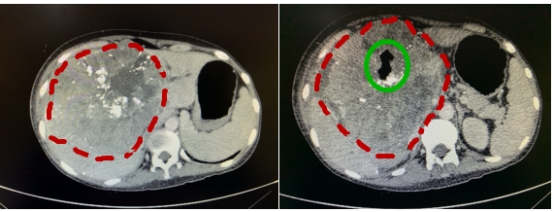

肝中叶巨大肿瘤侵犯胃、十二指肠合并穿孔、出血(红圈为肿瘤,绿圈为穿孔进的气体)